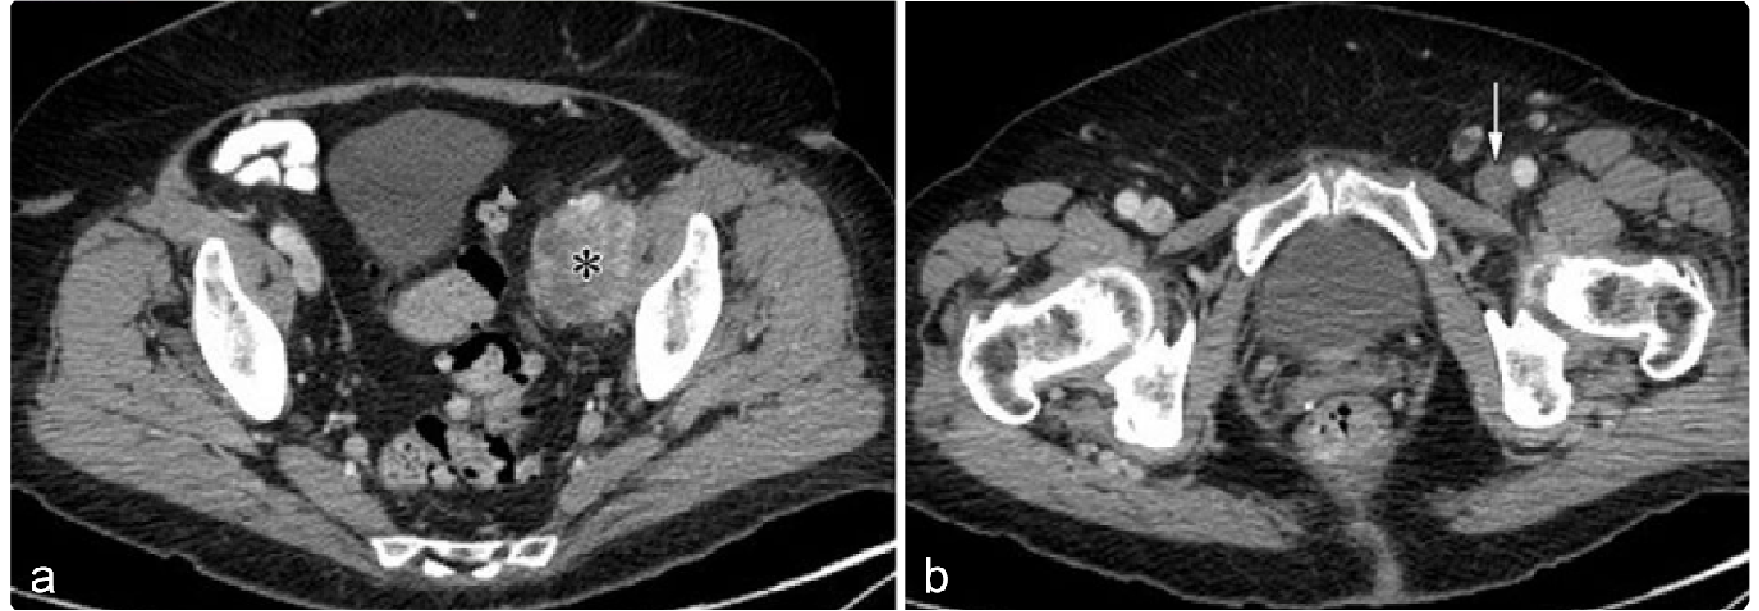

9ad706cca015cfbc11c4e89e74a3010e.png 病例 12:腹膜后(血管内/外)平滑肌肉瘤  49岁女性左侧腹膜后软组织肿块,不均质强化。T2WI上呈等及稍高混杂信号。T2WI冠状位示肿瘤上下径较长,肿瘤瘤体位于左侧卵巢静脉走行区。大体病理显示左侧卵巢静脉内可见肿瘤(*)

992516d395e1455b514acae6f30fd86f.png 病例 13:腹膜后(血管内)平滑肌肉瘤  76岁女性,左腿疼痛肿胀左侧盆壁髂外静脉走行区软组织肿块,不均质强化,左侧股静脉内可见血栓形成。